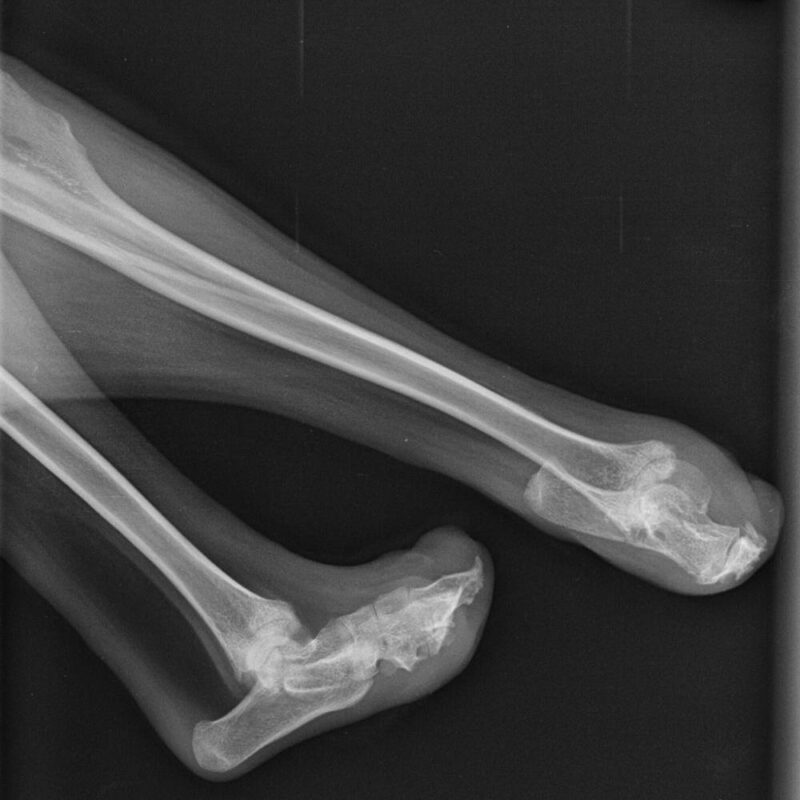

Amputationshöhen am vorderen und hinteren Lauf

Wieviel sollte vom Lauf erhalten sein um eine Prothese noch anpassen zu können?

mind. 50% von Elle und Speiche (Ullna / Radius) sollten erhalten sein um eine Prothese anpassen zu können, je mehr desto besser.

Ist das Handgelenk / Karpalgelenk erhalten, sind die Vorraussetzungen für eine Prothese gut. Bleibt mehr erhalten sind die Vorraussetzungen optimal, z.B. bei einer Pfotenamputation. Das Gleiche gilt für den hinteren Lauf mit dem Unterschied, dass keine Prothese mehr angepasst werden kann wenn über dem Tarsalgelenk / Sprunggelenk amputiert wird.

Hinterer Lauf:

Das Sprunggelenk / Tarsalgelenk muss erhalten werden / vorhanden sein, sonst ist eine Prothesenanpassung so gut wie unmöglich.

Wird zu viel amputiert / ein zu kurzer Stumpf, ist eine Prothese nicht mehr anzupassen da eine Prothesen-Fixierung und die sichere Steuerung der Prothese verloren gehen.